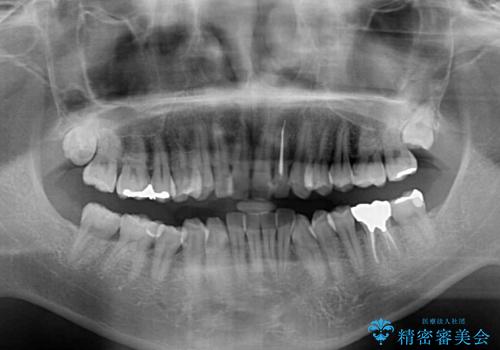

前歯のデコボコと下顎の八重歯 インビザラインによる矯正治療

- 前歯のデコボコや八重歯を気にして来院された患者様です。

インビザラインを用いて、歯列を整えることとしました。